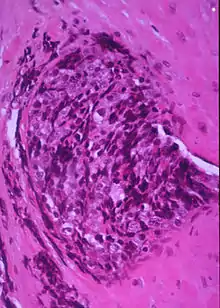

Display of small round blue cells characteristic of desmoplastic small round cell tumour.

In histopathology, a small-blue-round-cell tumour (abbreviated SBRCT), also known as a small-round-blue-cell tumor (SRBCT) or a small-round-cell tumour (SRCT), is any one of a group of malignant neoplasms that have a characteristic appearance under the microscope, i.e. consisting of small round cells that stain blue on routine H&E stained sections.

These tumors are seen more often in children than in adults. They typically represent undifferentiated cells. The predominance of blue staining is because the cells consist predominantly of nucleus, thus they have scant cytoplasm.[1][2]